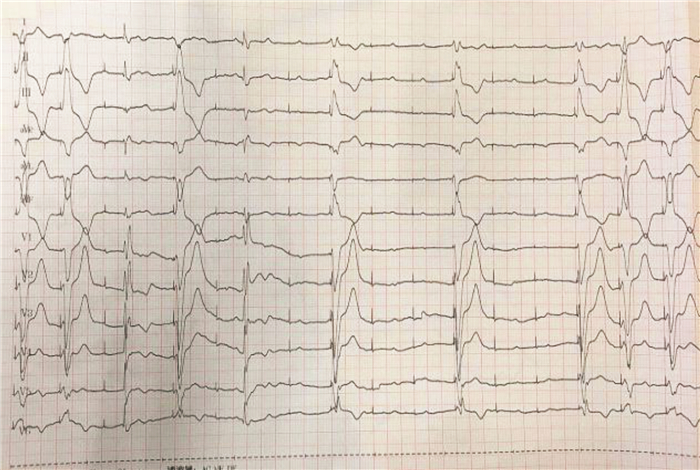

1 资料与方法患者女性,44岁。因“反复抽搐3 h”呼叫“120”求助。患者5 d前曾行经导管室间隔缺损封堵术(TCVSD),在乘出租车前往医院途中又反复抽搐3次,每次持续约十余秒,抽搐后很快恢复意识。救护人员达到现场时,患者神清,无抽搐,可行走。查体:P 95次/min, R 15次/min, BP 110/70 mmHg(1 mmHg=0.133 kPa),心肺查体无特殊,皮肤稍湿冷。将患者搬运上救护车后,心电监护显示窦性心律,心率95次/min,SpO2 92%,建立静脉通道,低流量吸氧。3 min后,患者再发阿-斯综合征,心电监护显示缓慢性心律失常,心律45次/min,考虑高度房室传导阻滞引起阿-斯综合征发作可能,立即予胸外按压,同时予阿托品0.5 mg静推,效果欠佳。立即黏贴一次性电极片,行经皮临时心脏起搏(TCP),后备起搏模式,设置起搏频率70次/min,起搏电流40 mA起,调节至60 mA,心电监护示起搏心律,频率70次/min,起搏成功后患者马上苏醒,生命体征平稳。予地西泮5 mg静推镇静后患者嗜睡,心率上升至110次/min,为窦性心律,停用TCP。2 min后,患者再次出现阿-斯综合征发作,行TCP治疗后亦很快苏醒,维持TCP治疗直至到达医院急诊科。TCP成功后心电图见图 1。到达急诊科时ECG示,窦性心律,完全性右束支传导阻滞(RBBB)。急查血钾3.0 mmol/L,紧急补钾治疗同时请心内科会诊。心内科会诊医生要求维持TCP治疗,并由急救人员协助转运到心内科放置心内膜下临时起搏器。患者在放置临时心脏起搏器的过程中,静滴异丙肾上腺素[0.03~0.06 μg/(mL·min)]后出现窦速(心率140次/min),随后出现Ⅲ度房室传导阻滞(Ⅲ度AVB),并出现长间期心室停搏,患者阿-斯综合征再次发作,立即行TCP治疗,持续到约30 min后临时心脏起搏放置调试完毕。心内科临时起搏放置后心电图见图 2,可见房室分离,交界区逸搏,临时起搏间歇性失夺获。患者入院后诊断一过性Ⅲ度AVB,应用糖皮质激素治疗2 d后心律失常未发作,于1周后出院,出院时血钾3.68 mmol/L。

| 图 1 患者TCP成功后心电图 |